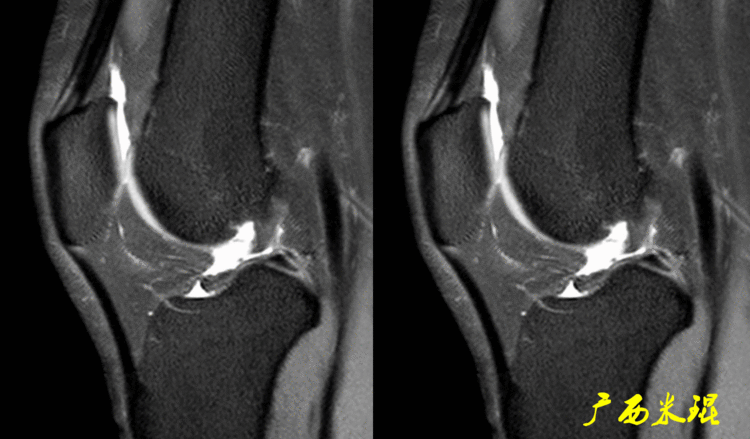

如同下面这张MR,左侧图像为手术前的,右侧图像为手术后的,术后病人疼痛等症状仍然存在,复查MR见外侧半月板前角分层,半月板前角的处理是有一定难度的,有经验的医生会考虑可能是手术者对前角的处理不够熟悉,没有通过另外的办法处理半月板前角的水平裂,不过也只能是猜测而已。所以,对于半月板术后的评估,症状的消失比MR重要!